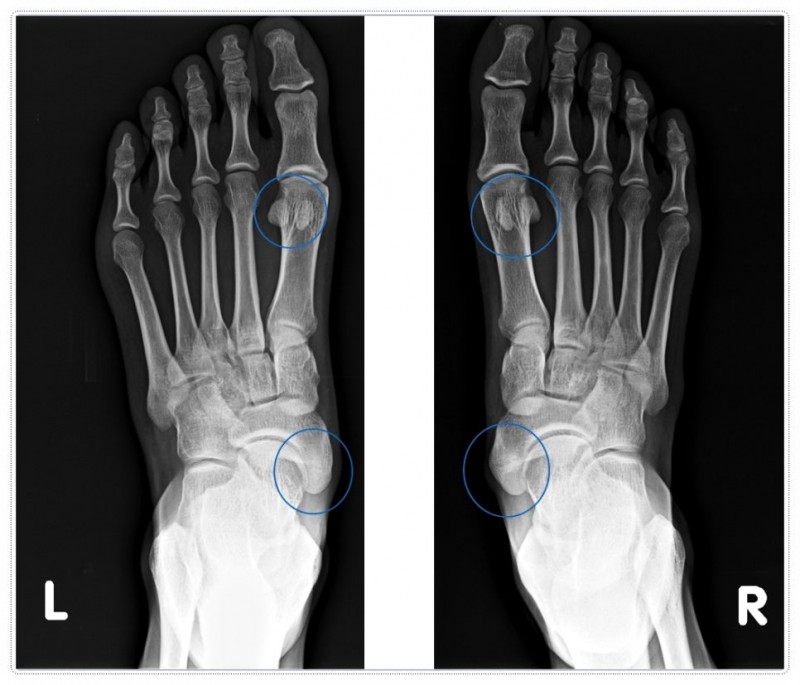

지간신경종은 발가락 사이 신경이 반복적으로 눌리며 생기는 통증·저림 증상입니다.